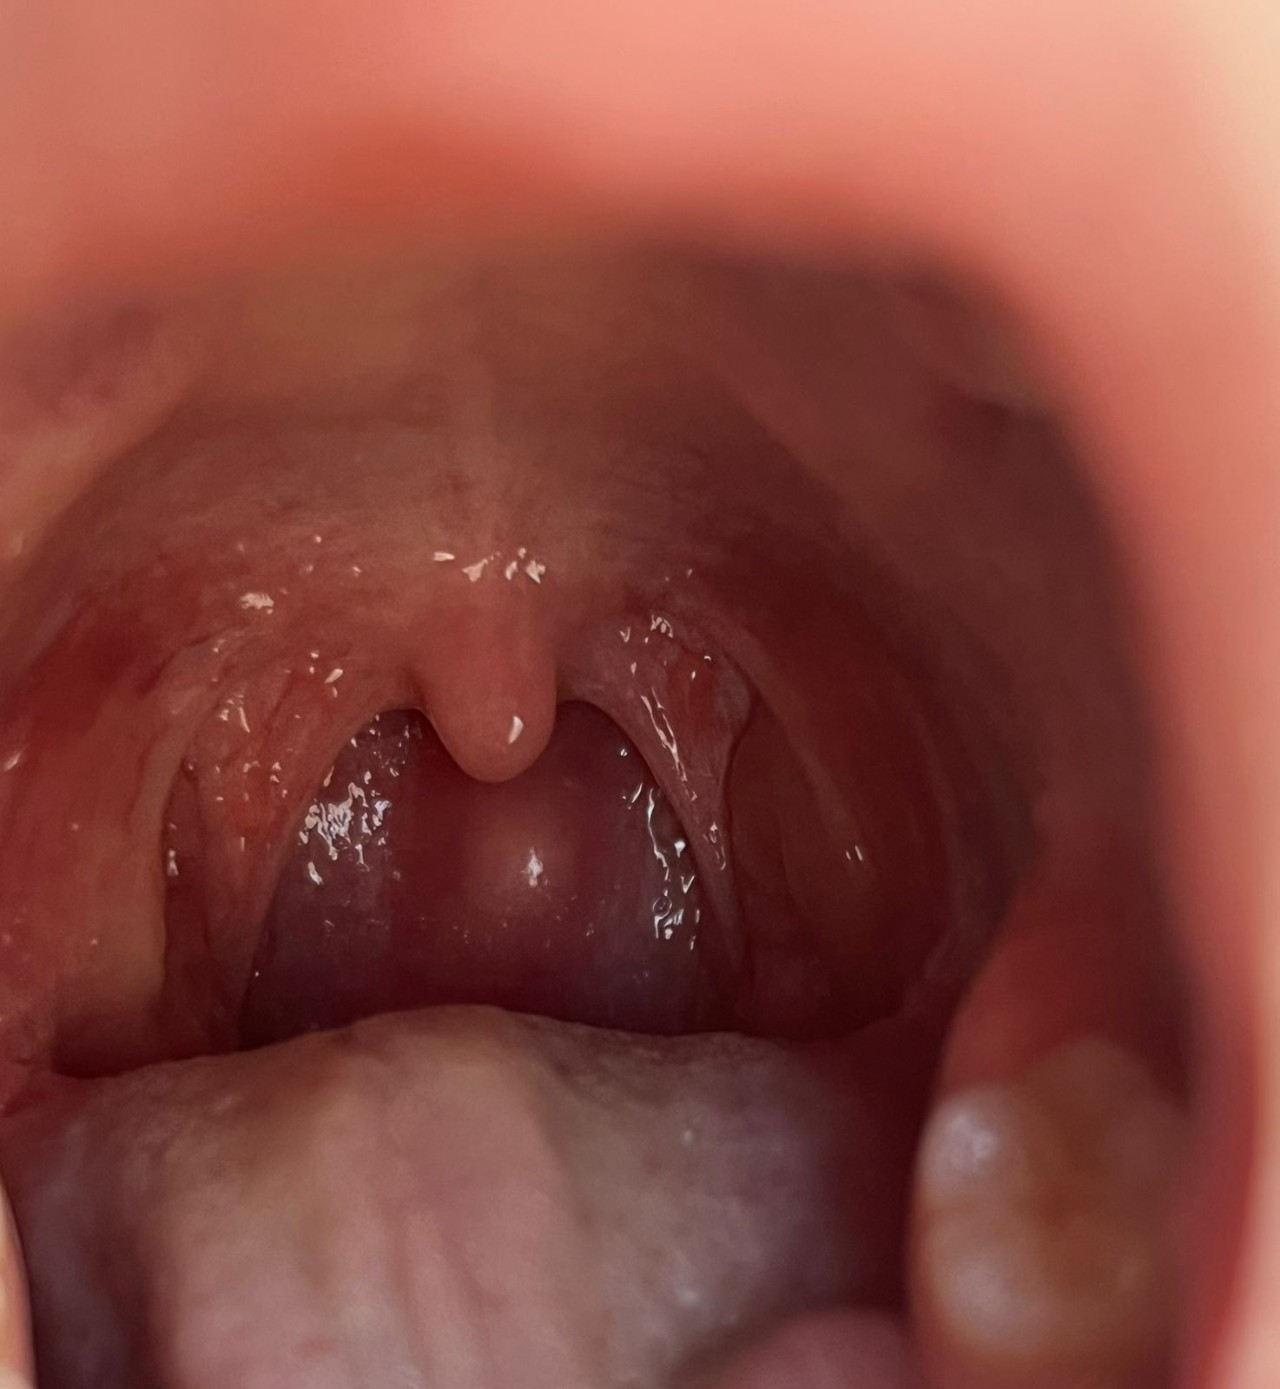

Здравствуйте, у ребенка 7 лет с января 2026 года на задней стенке глотки обнаружили вот такую шишку. Делали пунктирование на заглоточный абцесс- отрицательно, шишечка плотная.

сказали наблюдать.

Что лучше сделать МРТ шеи? Покажет что за шишечка? Или сразу идти на удаление? На что похожа данная шишка?

травм шеи нет, похожа ли на лимфоидную ткань? Болела гайморитом в октябре-декабре2025г